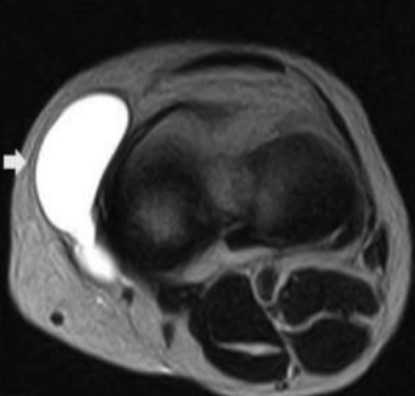

Киста Бейкера - осложнение бурсита подколенной сумки на МРТ

Хронический процесс часто является следствием неадекватного лечения острого воспаления. Заболевание развивается на фоне постоянной вибрации или механического воздействия на сустав.

Длительно существующую патологию отличает латентное или медленно прогрессирующее течение, с периодическими эпизодами обострения. Хроническое воспаление бурсы приводит к значительному накоплению экссудативной жидкости в полости синовиальной сумки, что способствует формированию кистозных образований. Магнитно-резонансную томографию проводят в рамках предоперационного исследования.